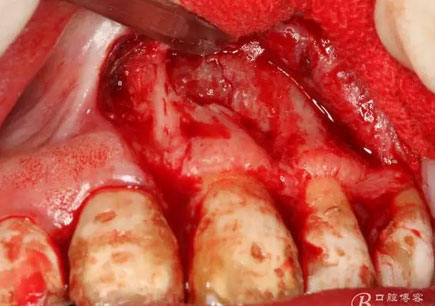

圖7.11近中的垂直切口

圖8.垂直切口+齦溝內(nèi)水平切口,水平切口延至23遠(yuǎn)中乳頭。

圖9.切口的交界處翻瓣,注意翻全厚瓣。

圖10.翻開(kāi)粘膜瓣發(fā)現(xiàn)有唇側(cè)部分骨壁不規(guī)則缺損。

圖11.逐漸去骨薄如蟬翼的骨壁,暴露出完整的囊壁